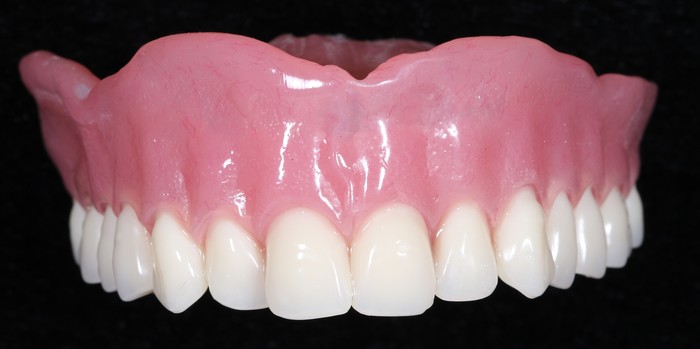

Если вы думаете, что пациентка ушла из клиники без зубов, то вы ошибаетесь. Перед удалением в обязательном порядке ортопед снимает слепки челюстей. Далее техник изготавливает полные съемные протезы в лаборатории.

Ниже представлен пример временного полного съемного протеза верхней челюсти.

Пациентка с протезом, установленным сразу после удаления зубов и имплантатов.

Уже секс, согласны? С ним она будет ходить до момента его замены на постоянную конструкцию.

По прошествии двух месяцев после удаления можно приступать к имплантации.

Далее ортопедом были сняты слепки, а техник в лаборатории изготовил вот такой постоянный протез с опорой на имплантатах.